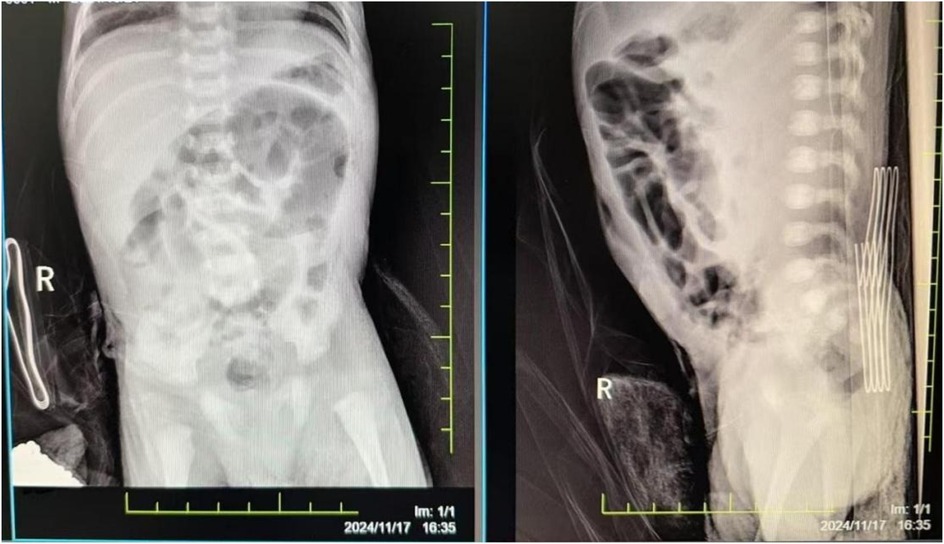

The damage to the gastrointestinal system is due to the redistribution of blood flow initiated to protect more critical organs, with significant reduction in intestinal blood supply. This leads to edema, increased permeability, ulceration, necrosis, and bleeding of the gastrointestinal mucosa, gastrointestinal dysfunction, and reperfusion damage, resulting in particularly severe intestinal injury. Severe asphyxia-related gastrointestinal damage is positively correlated with the incidence of multiple organ dysfunction (2). Although protective measures, including fasting, were implemented for the gastrointestinal system after admission, the infant developed necrotizing enterocolitis with perforation on the fourth day after birth (see Figure 2). Intraoperatively, extensive congestion and edema of the small intestine from 10 cm to 40 cm from the ileocecal valve were observed, covered with purulent exudate, with poor intestinal wall elasticity; intestinal wall rupture, edema of the mesenteric root, and numerous gas bubbles were visible. An ileal resection, intestinal anastomosis + ileostomy (Santulli procedure) + abdominal drainage were performed. After confirming the return of intestinal function, breastfeeding was initiated on the fourth day after surgery, gradually increasing milk volume to full enteral nutrition. Subsequently, due to the development of cholestasis, the feeding was changed to an extensively hydrolyzed milk formula after consultation with a gastroenterologist. On the 21st day after surgery, the infant again had bloody stools, and an abdominal radiograph suggested recurrent necrotizing enterocolitis (see Figure 3). Immediate fasting was initiated, and parenteral nutrition support was started, along with cefoperazone/sulbactam for anti-infection treatment.

Figure 3. The abdominal radiograph on postoperative day 21 suggests recurrent necrotizing enterocolitis.